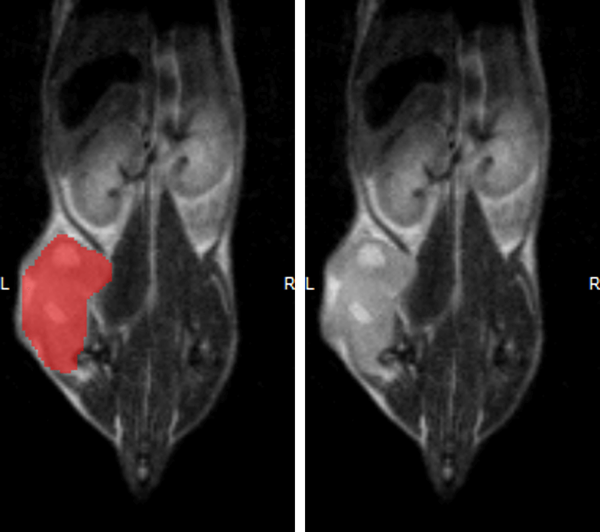

Hindlimb tumor growth: Monitoring the growth of xenograft tumor grown in the mouse hindlimb is identified with T2-weighted images. Segmentation of tumor region of interests (in red) on each tumor-containing slice allows accurate volume quantification. Image Credit: Scintica Instrumentation Inc

Monitoring the growth of xenograft tumor grown in the mouse hindlimb is identified with T2-weighted images. Segmentation of tumor region of interests (in red) on each tumor-containing slice allows accurate volume quantification. Image Credit: Scintica Instrumentation Inc